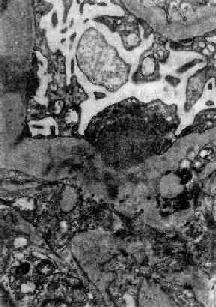

图12-7 弥漫性毛细血管内增生性肾小球肾炎

肾小球内细胞数量增多,系膜细胞和内皮细胞增生并有少量中性白细胞浸润,毛血管腔狭窄